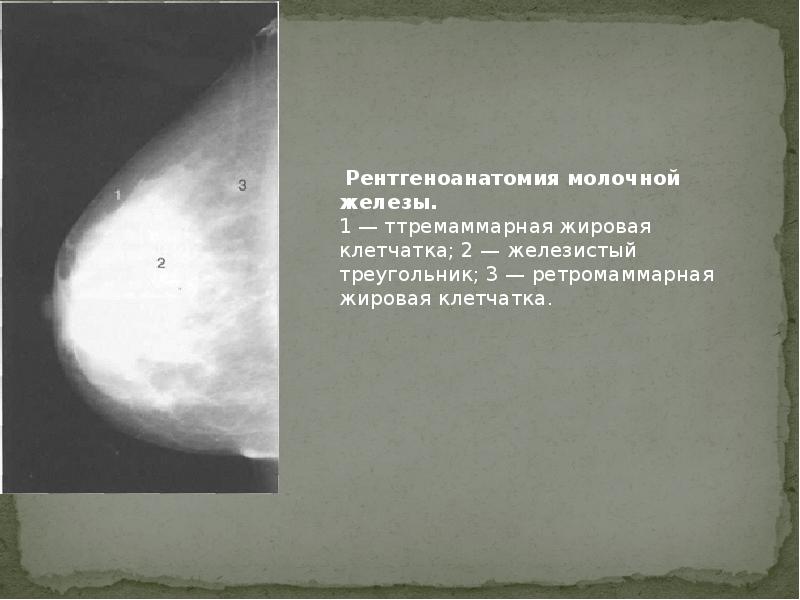

Аномалии молочной железы: медицинские примеры и визуализация

Раздел: Мудрость в деталях